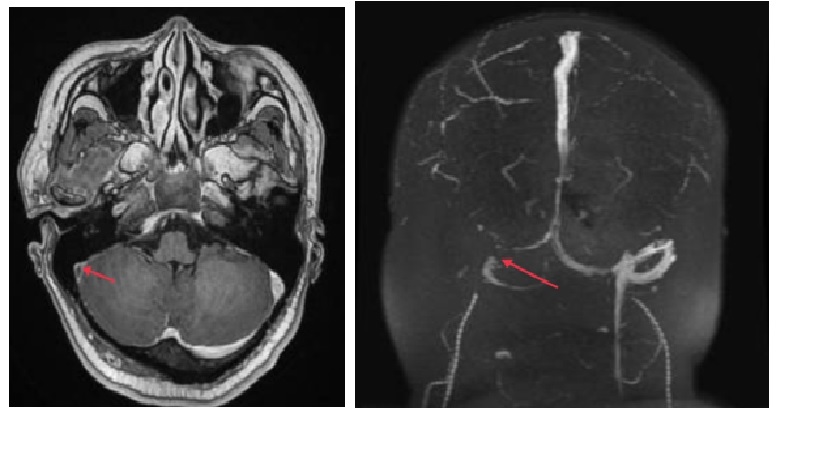

MRI: huyết khối xoang ngang; MRV : Tắc nghẽn xoang ngang phải

Huyết khối xoang ngang phải /Nhồi máu não chuyển dạng xuất huyết thùy thái dương phải.

MRI và Magnetic Resonance Venogram

MRI có cản quang và cộng hưởng từ tĩnh mạch (MRV) là phương thức chẩn đoán ưu tiên nhất cho CSVT, và sự xuất hiện của huyết khối trên các chuỗi MRI khác nhau phụ thuộc vào thời gian(appearance of thrombus on different MRI sequences are time dependent).

Trong vòng 5 ngày, nó xuất hiện isointense trên T1 và hypointense trên T2. Trong 6–15 ngày, huyết khối xuất hiện hyperintense trên cả hai chuỗi T1 và T2. Sau 15 ngày, chúng xuất hiện isointense trên các chuỗi T1 và iso- or hyperintense trên các chuỗi T2. Bốn tháng sau, không có bất thường nào trên T1 và các bất thường tinh tế trên chuỗi T2 có thể được phát hiện.

MRI xuất hiện ở dạng cấp tính xảy ra do lượng deoxyhemoglobin trong huyết khối tăng lên, và những thay đổi thấy ở dạng bán cấp là do nồng độ methemoglobin tăng lên. Sự vắng mặt của những thay đổi trong chuỗi tín hiệu T1 và mô hình dòng chảy bình thường (normal flow pattern ) trên chuỗi T2 làm cho chẩn đoán đặc biệt khó khăn ở dạng cấp tính của bệnh